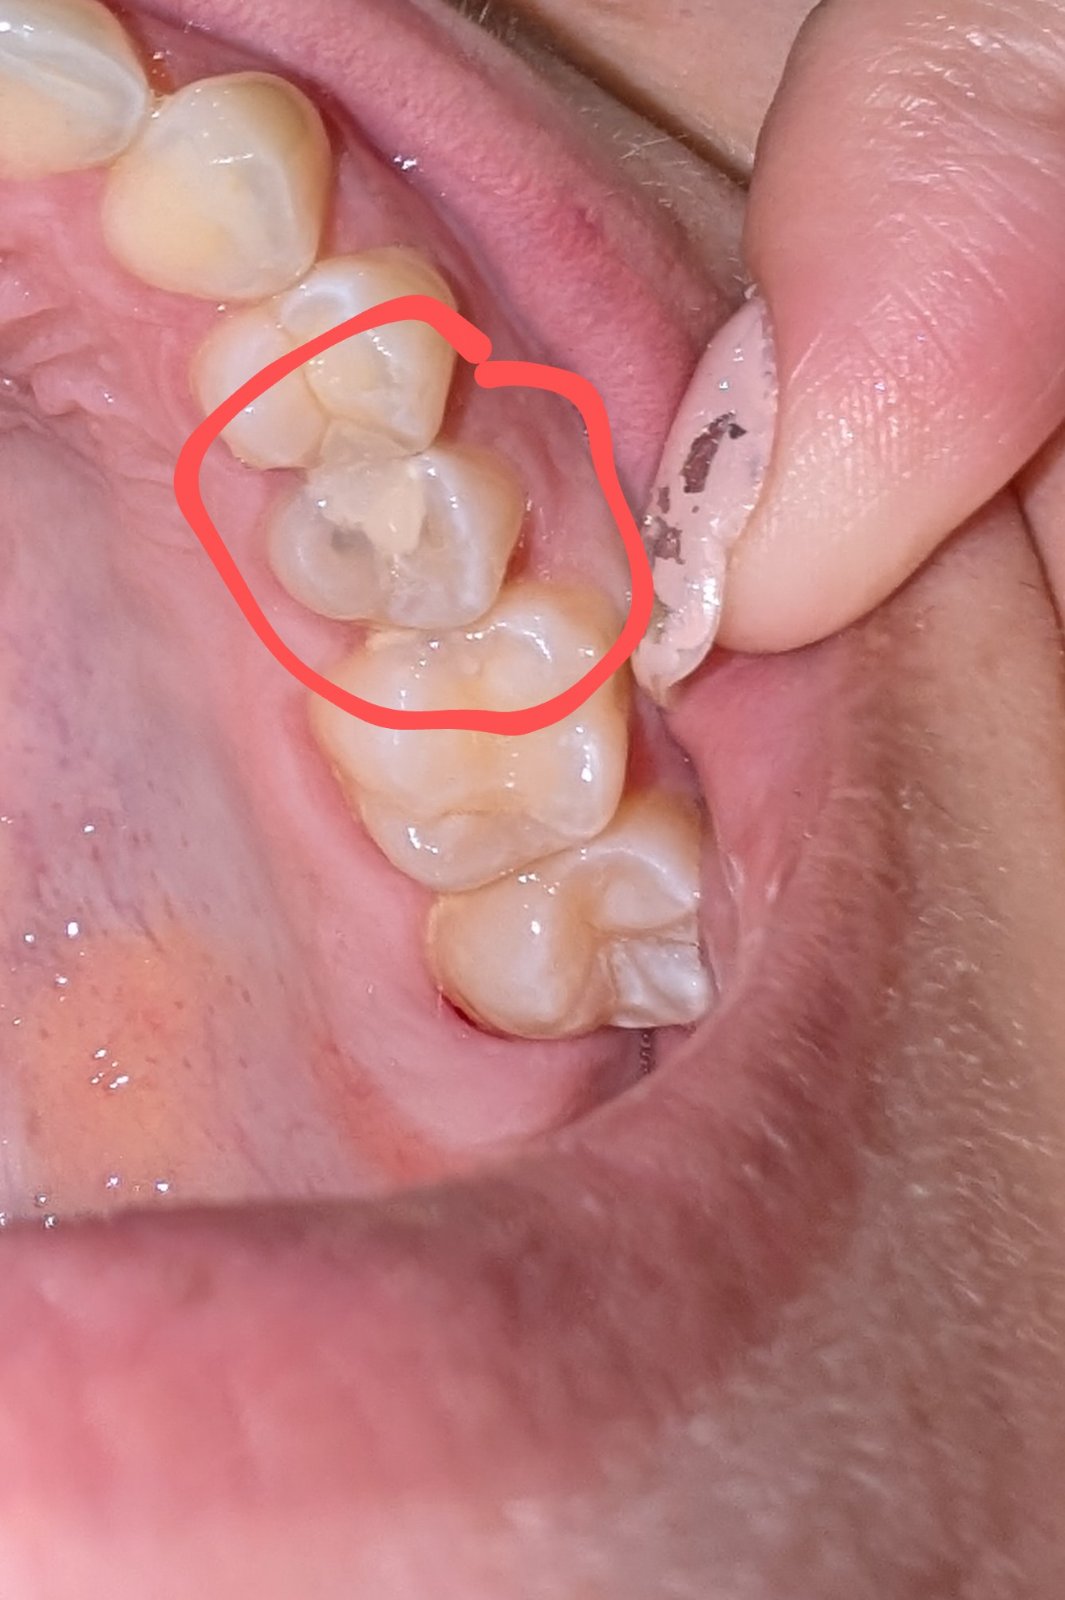

Zubárka spojila zuby plombou

Mela jsem kaz pod plombou a od toho mi trochu chytl druhy

Tak mi to zubarka vyvrtala.

A dala bilou plombu. Jenze jak jsem to mela umrtvene tak jsem nevedela ze mi plombou spojila oba zuby. Mam celkove discomfort u toho zubu a I citlivost a bolesti

Dentalni niti SE tam taky nedostanu pochopitelne

Máš to urobené zle. Oba zuby musia byť samostatne stojace jednotky a musí byť medzi nimi medzera. Čiže zrejme potrebuješ výplň na oba,ale samostatne,nie spojiť 🧐